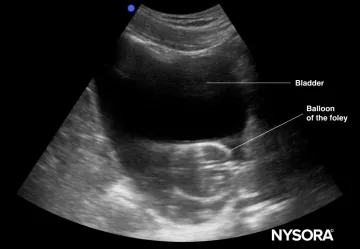

Curioso della scienza dietro i cateteri di Foley? Immergiamoci! I cateteri di Foley sono ingegnosi dispositivi medici progettati per drenare l'urina dalla vescica, con un tubo flessibile con un pallone gonfiabile a un'estremità per mantenerlo saldamente in posizione. Li troverai spesso in azione negli ospedali, sia durante gli interventi chirurgici, per i pazienti che affrontano la conservazione urinaria o per coloro che hanno bisogno di un po 'di aiuto in più per arrivare in ba

Il catetere urinario, comunemente noto come "Foley", è un tubo di drenaggio dotato di un palloncino di ritenzione progettato per raccogliere l'urina in un sistema chiuso, riducendo così al minimo il rischio di infezioni. L'assistenza di base per un catetere Foley prevede la pulizia del catetere con sapone lieto e acqua calda due volte al giorno e lubrificare la punta per i pazienti maschi per prevenire l'irritazione. Quando si cambiano i sacchi di raccolta, è essenzia

Il catetere Foley, spesso l'eroe sconosciuto degli ospedali, svolge un ruolo cruciale nella cura dei pazienti, in particolare nella gestione delle questioni urinarie. Questo snello tubo, realizzato in silicone o lattice di livello medico, viene inserito nella vescica e fissata da un pallone gonfiabile, che mostra l'innovazione nella progettazione medica. La sua versatilità si estende oltre il semplice drenaggio urinario; È un giocatore chiave nel recupero post-chirurgia, nel monitor